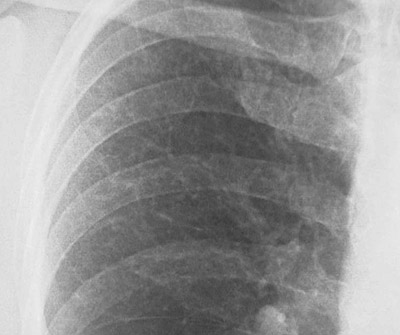

In the closer view shown here of a chest radiograph in a patient with progressive pulmonary fibrosis, the lace-like pattern is apparent.